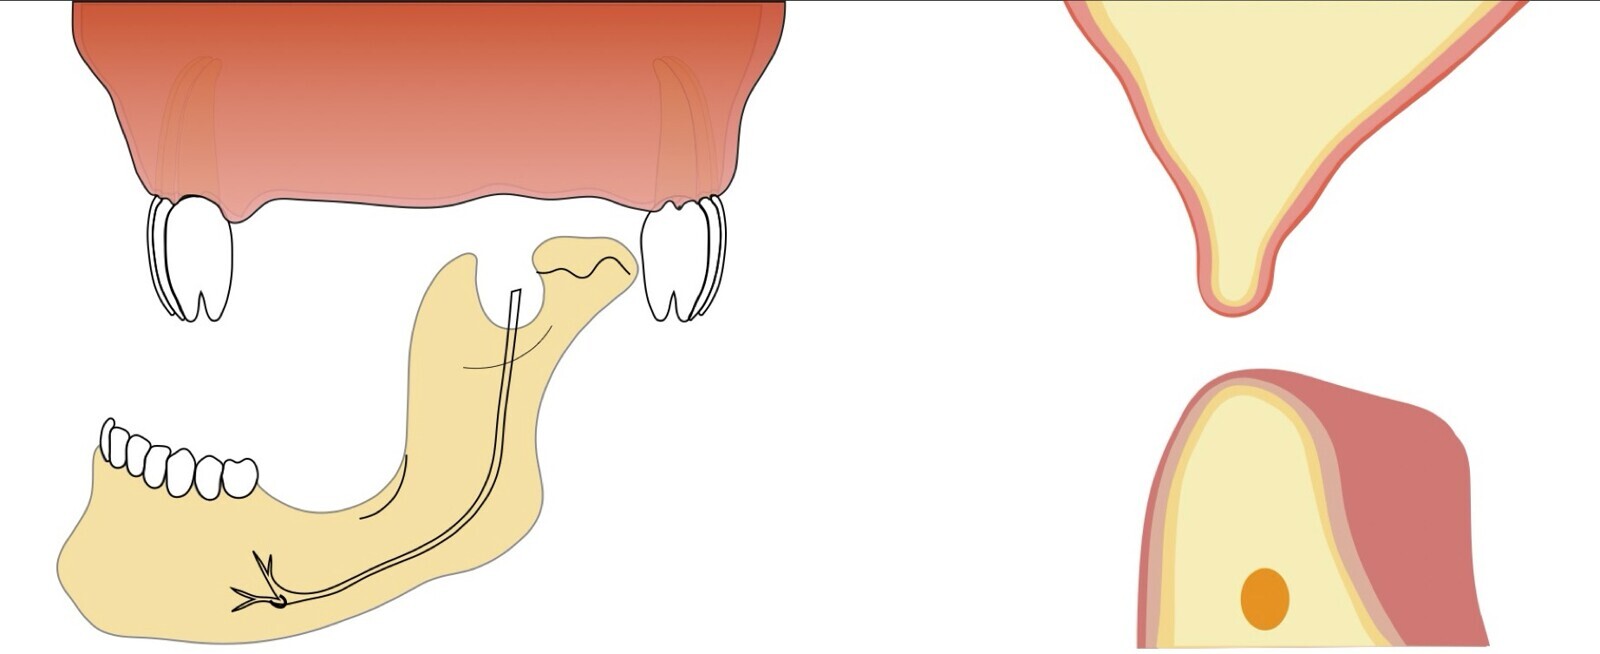

Si la zona donadora es la sínfisis mentoniana, se deben tomar en cuenta los límites de seguridad para la extracción del injerto, que son 5 mm alejado de los ápices, y 5 mm alejado del agujero mentoniano (Figuras 2 y 3).

Figura 3. Imagen comparativa de corte con piezoeléctrico y trefinas. Foto: cortesía Dr. Claudio Nóia.